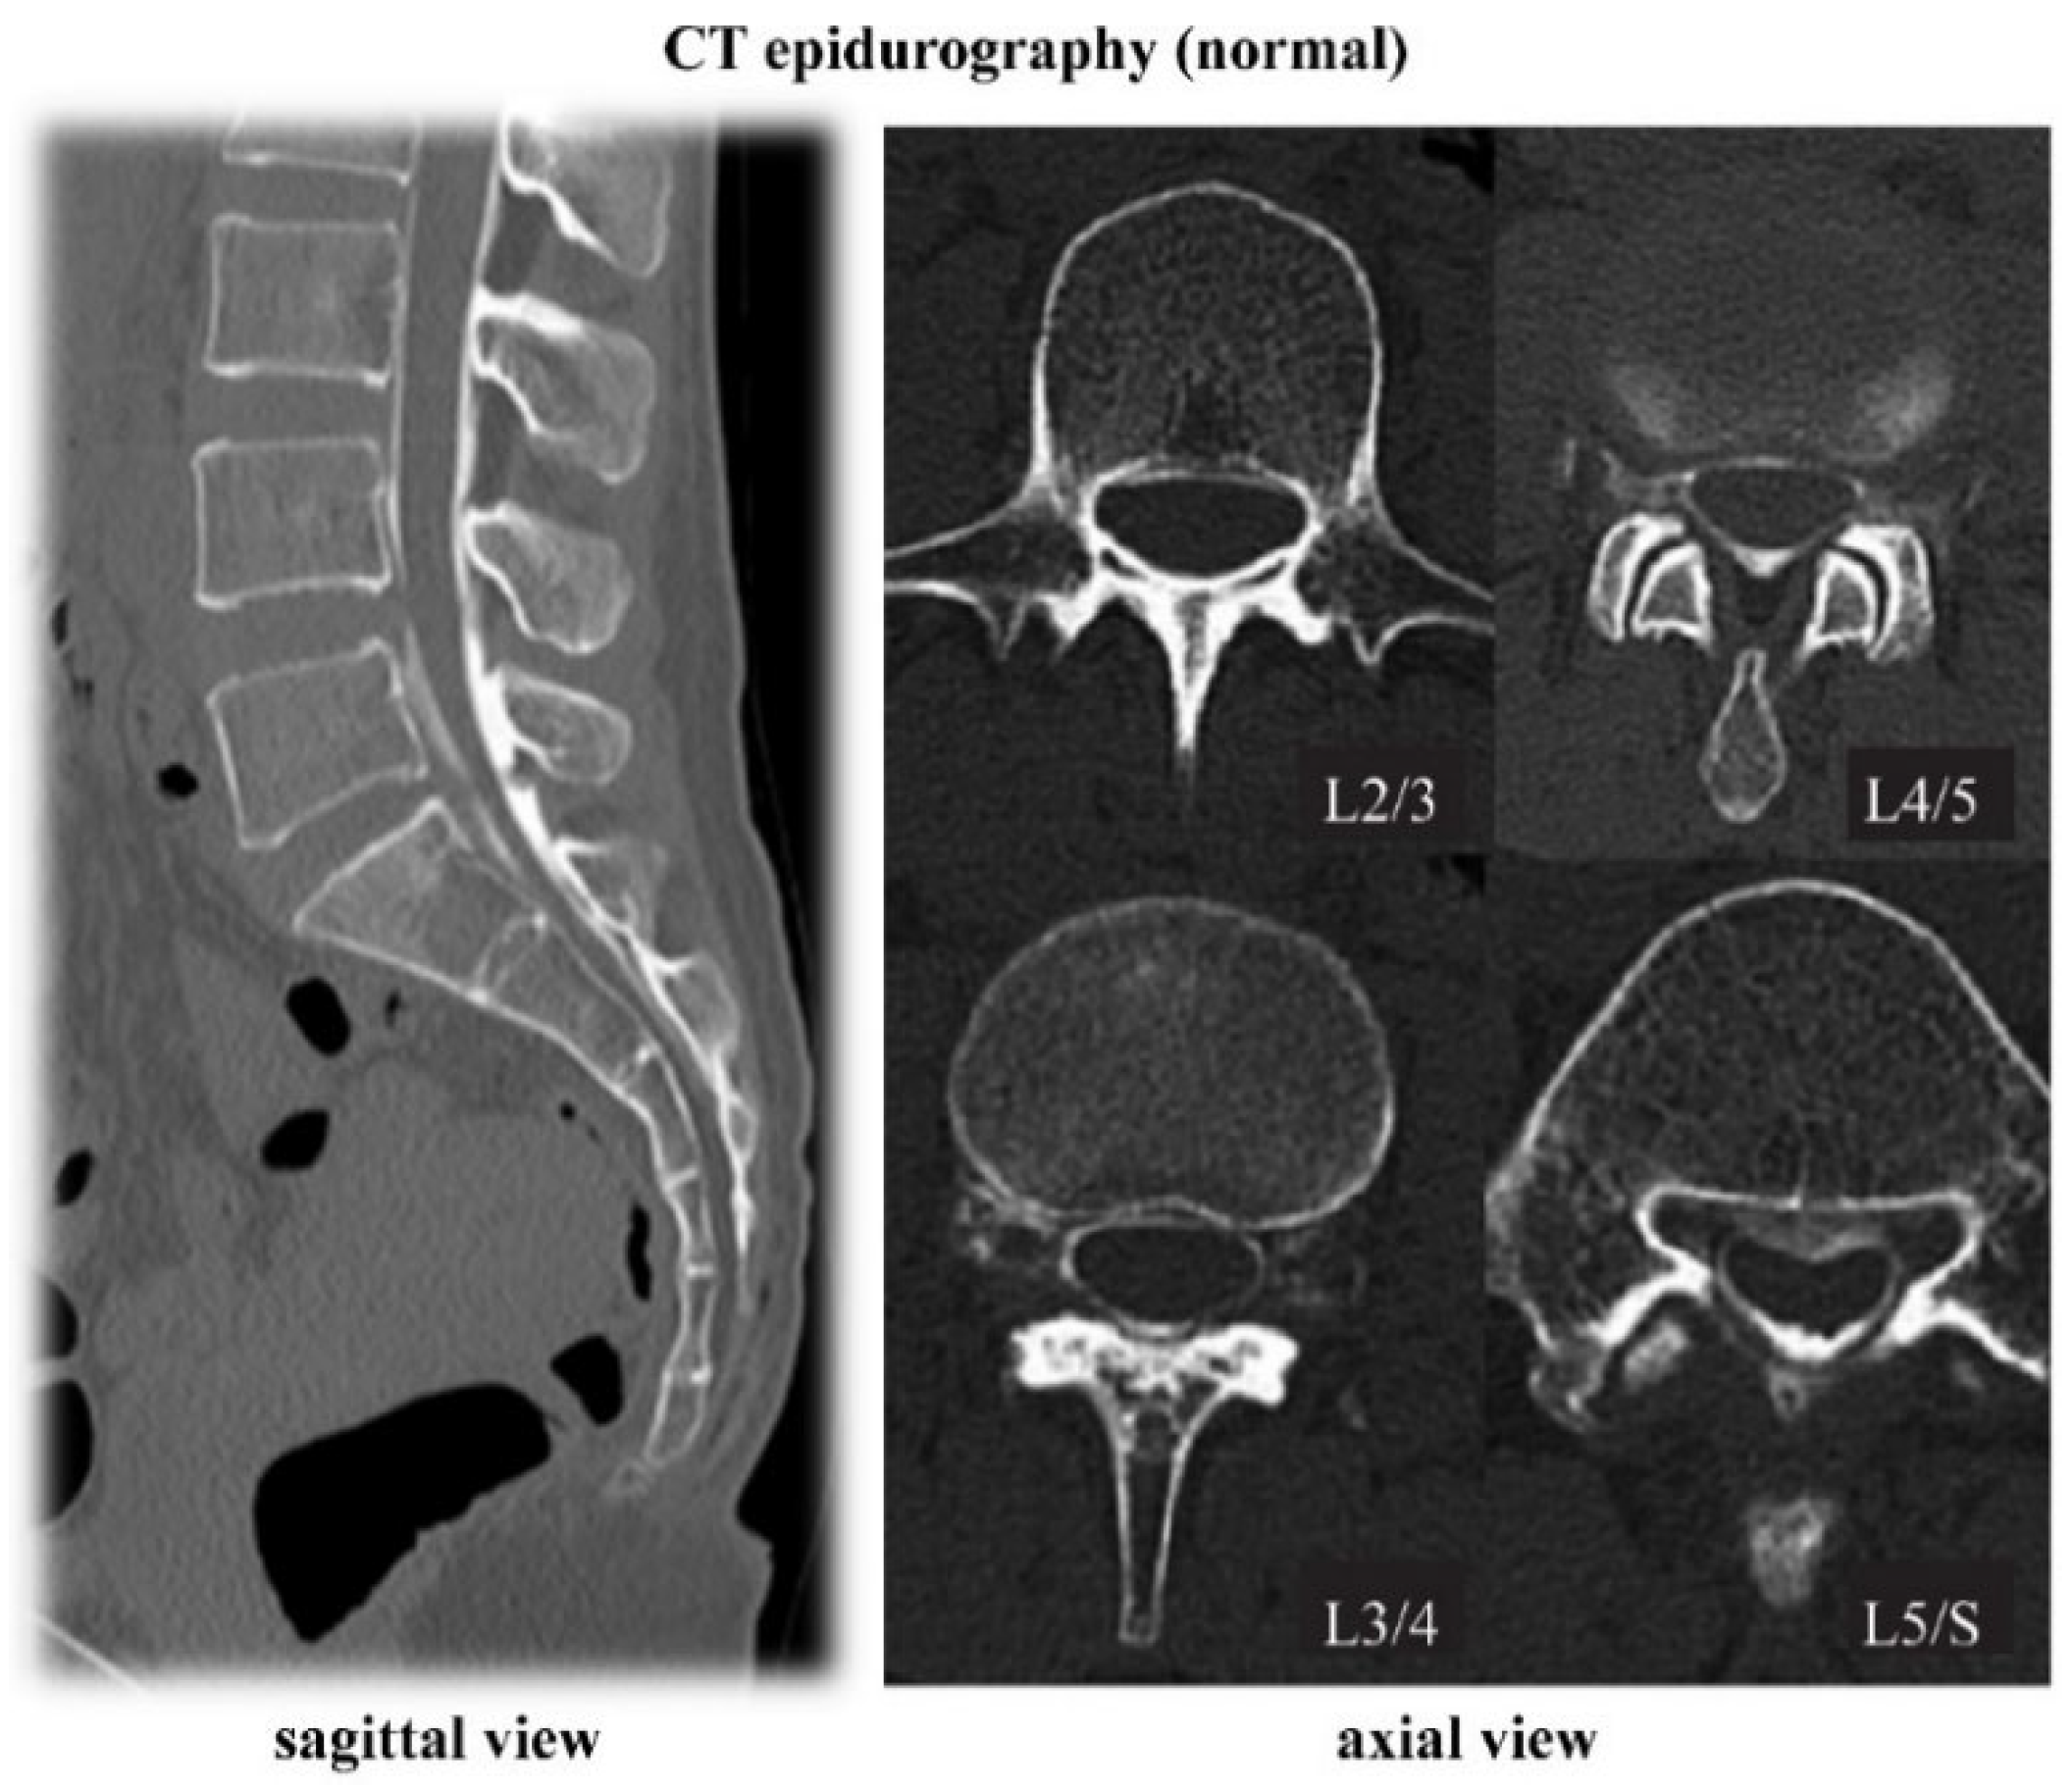

4.1. CT Epidurography